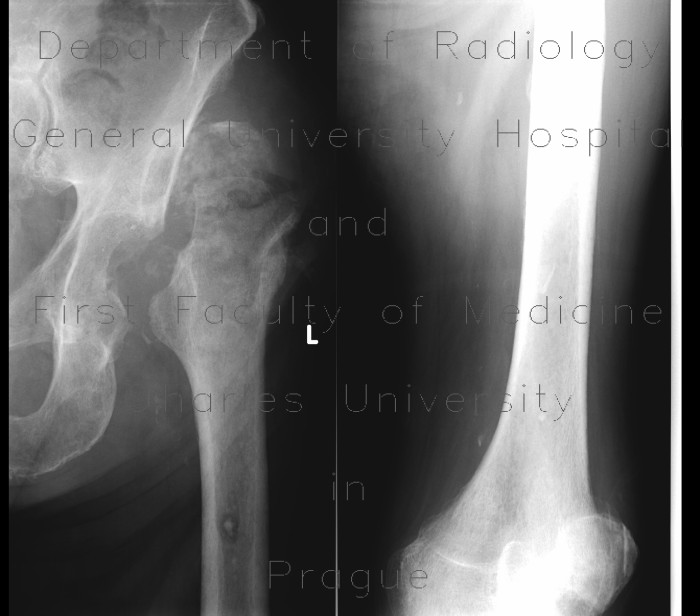

Radiology case: Bone sequestration, osteomyelitis

Bony sequestrum: a radiologic review | SpringerLink

Bony sequestrum | pacs